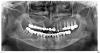

vasar Опубликовано 1 апреля, 2013 Поделиться Опубликовано 1 апреля, 2013 Добрый день!Мне несколько клиник после просмотра снимка предложили этот метод имплантации.Хотел узнать мнение профессионалов о методе одноэтапной имплантации с немедленной нагрузкой.Очень бы не хотелось растягивать эту процедуру на год или больше. Снимок прилагаю. 1 Ссылка на комментарий

Bier Опубликовано 1 апреля, 2013 Поделиться Опубликовано 1 апреля, 2013 На нижней челюсти в вашем случае вполне можно, на верхней нужен синуслифтинг и сразу имплантаты не нагрузить Ссылка на комментарий

Bier Опубликовано 1 апреля, 2013 Поделиться Опубликовано 1 апреля, 2013 Не знаю зачем тут КТ, у вас огромные пазухи, тут даже одноэтапно с синуслифтингом не во всех местах получится сделать, а уж чтобы еще и нагрузить сразу... Ну может я не владею конечно секретными методиками... всякое бывает Ссылка на комментарий